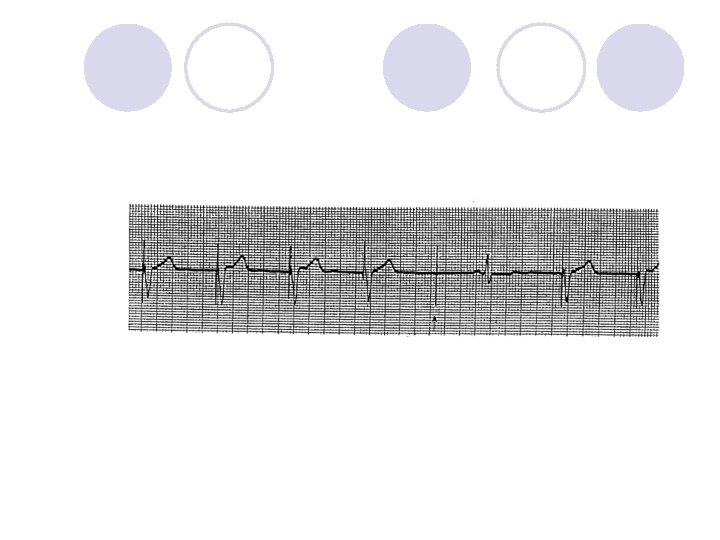

Is This Normal Device Operation?

What Device Operation is This?

What is missing?